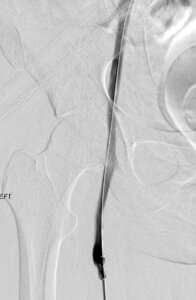

Post-Lysis Image 1

A 135 x 50 cm infusion length thrombolysis catheter was placed and positioned within the femoral vein extending to the iliocaval bifurcation. Overnight lysis was performed and a repeat venogram (left image) was performed demonstrating resolution of femoral thrombus.

Post-Lysis Image 2

A pelvic venogram performed after overnight lysis demonstrates significant reduction in iliac thrombus, however with residual chronic thrombus and/or stenosis involving the common iliac vein.